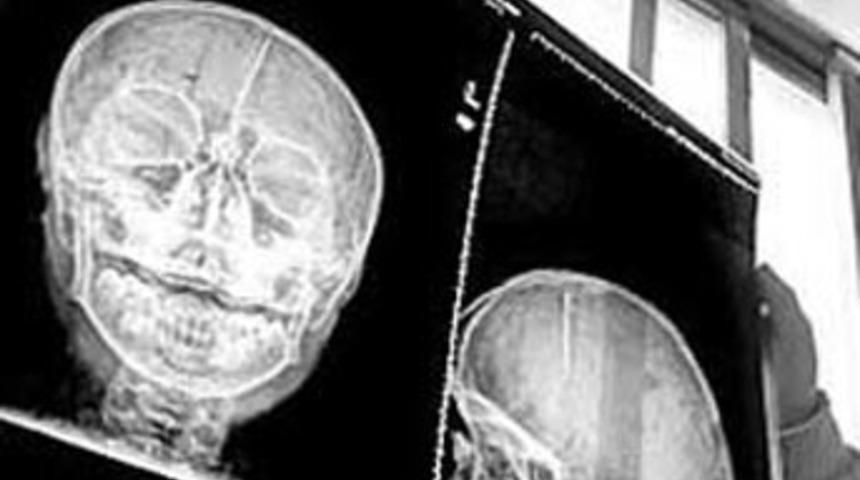

Gerçek adı açıklanmayan 11 yaşındaki küçük kız da, ailesinin hışmına uğramış. Bu hafta ameliyata alınan Pingping'in (doktorların kendisine taktığı isim) kafasındaki iğne çıkarıldı. Doktorlar bu iğnenin, kızın akıl sağlığındaki bozukluğa da sebep olduğunu düşünüyorlardı.

Pingping'in kafasından çıkarılan iğnenin üzerindeki pas tabakası, en az 10 yıldır çocuğun kafasında olduğunu gösteriyor.